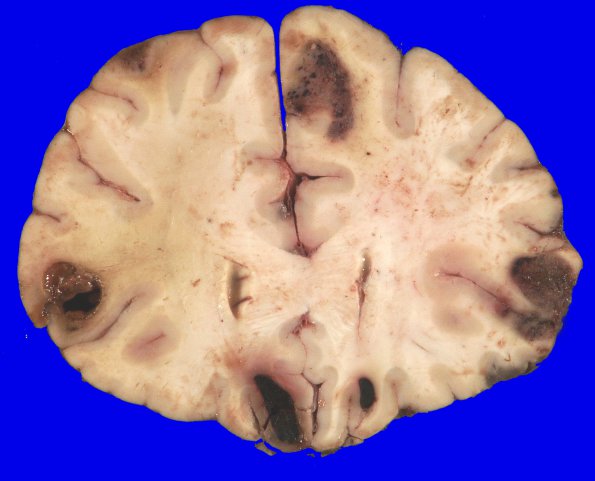

2B4-7 Coronal sections of the cerebral hemispheres reveal multiple gray-brown lesions at the gray-white matter junction in all areas of the neocortex, as well as in the right thalamus and bilateral cerebellar hemispheres. Some of the lesions, appear necrotic and liquefactive, with dark red-brown semi-solid material within a circumscribed cavity. The largest lesion is in the anterior right temporal cortex, measuring approximately 3.4 cm. There is an area of discoloration of the white matter in the superficial left frontal cortex. In the left parieto-occipital cortex, there is an area of white-yellow, caseous-appearing material within primarily white matter consistent with radiation effect.